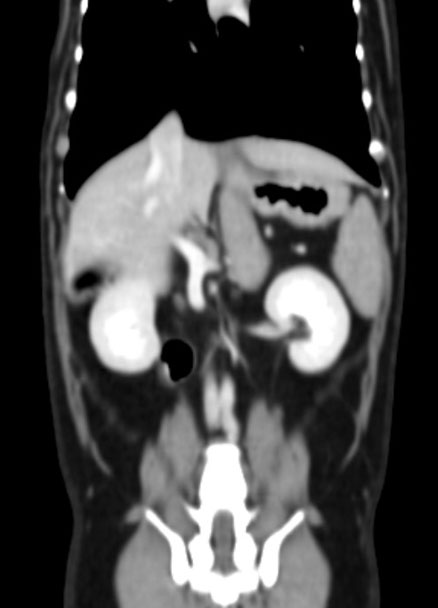

| 복부 | 간, 비장, 신장, 위장관 종양 및 결석, 부신, 림프절 등 |

혈관 조영(Angio CT)을 통한 혈관 이상 진단

복부 장기의 종양, 염증, 결석, 기형 등 고해상도 분석